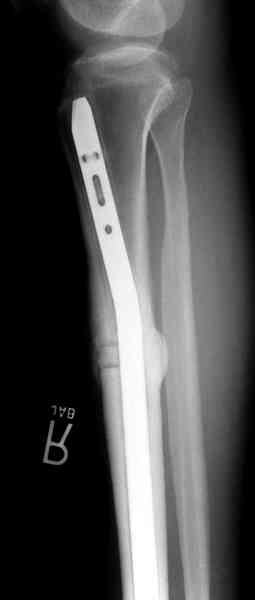

Недавно на нашей ежемесячной Morbidity&Mortality conference мы

разбирали похожий случай, ложный сустав большеберцовой кости после

резекции опухоли.

Оперирован в военном госпитале с заменой сегмента аллокостью

большеберцовой кости и после демобилизации явился для постоянного

наблюдения по месту жительства.

Наши имели проблему со сращением, пришлось им сделать динамизацию,

дополнительную аутопластику.

Имя     : 3 adamantioma ap prox plate.jpg